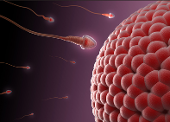

WHAT IS INFERTILITY ( men&women)

Infertility is defined as the inability to conceive after

12 months of unprotected sexual intercourse. Infertility may be

attributed to the man, the woman, or both partners. Infertility does

not mean that a couple is sterile and will never have a child.

Approximately half of all couples who seek help for infertility will

eventually conceive a child. There are several treatments available that

may help to improve the chances of a conception and a successful

pregnancy.